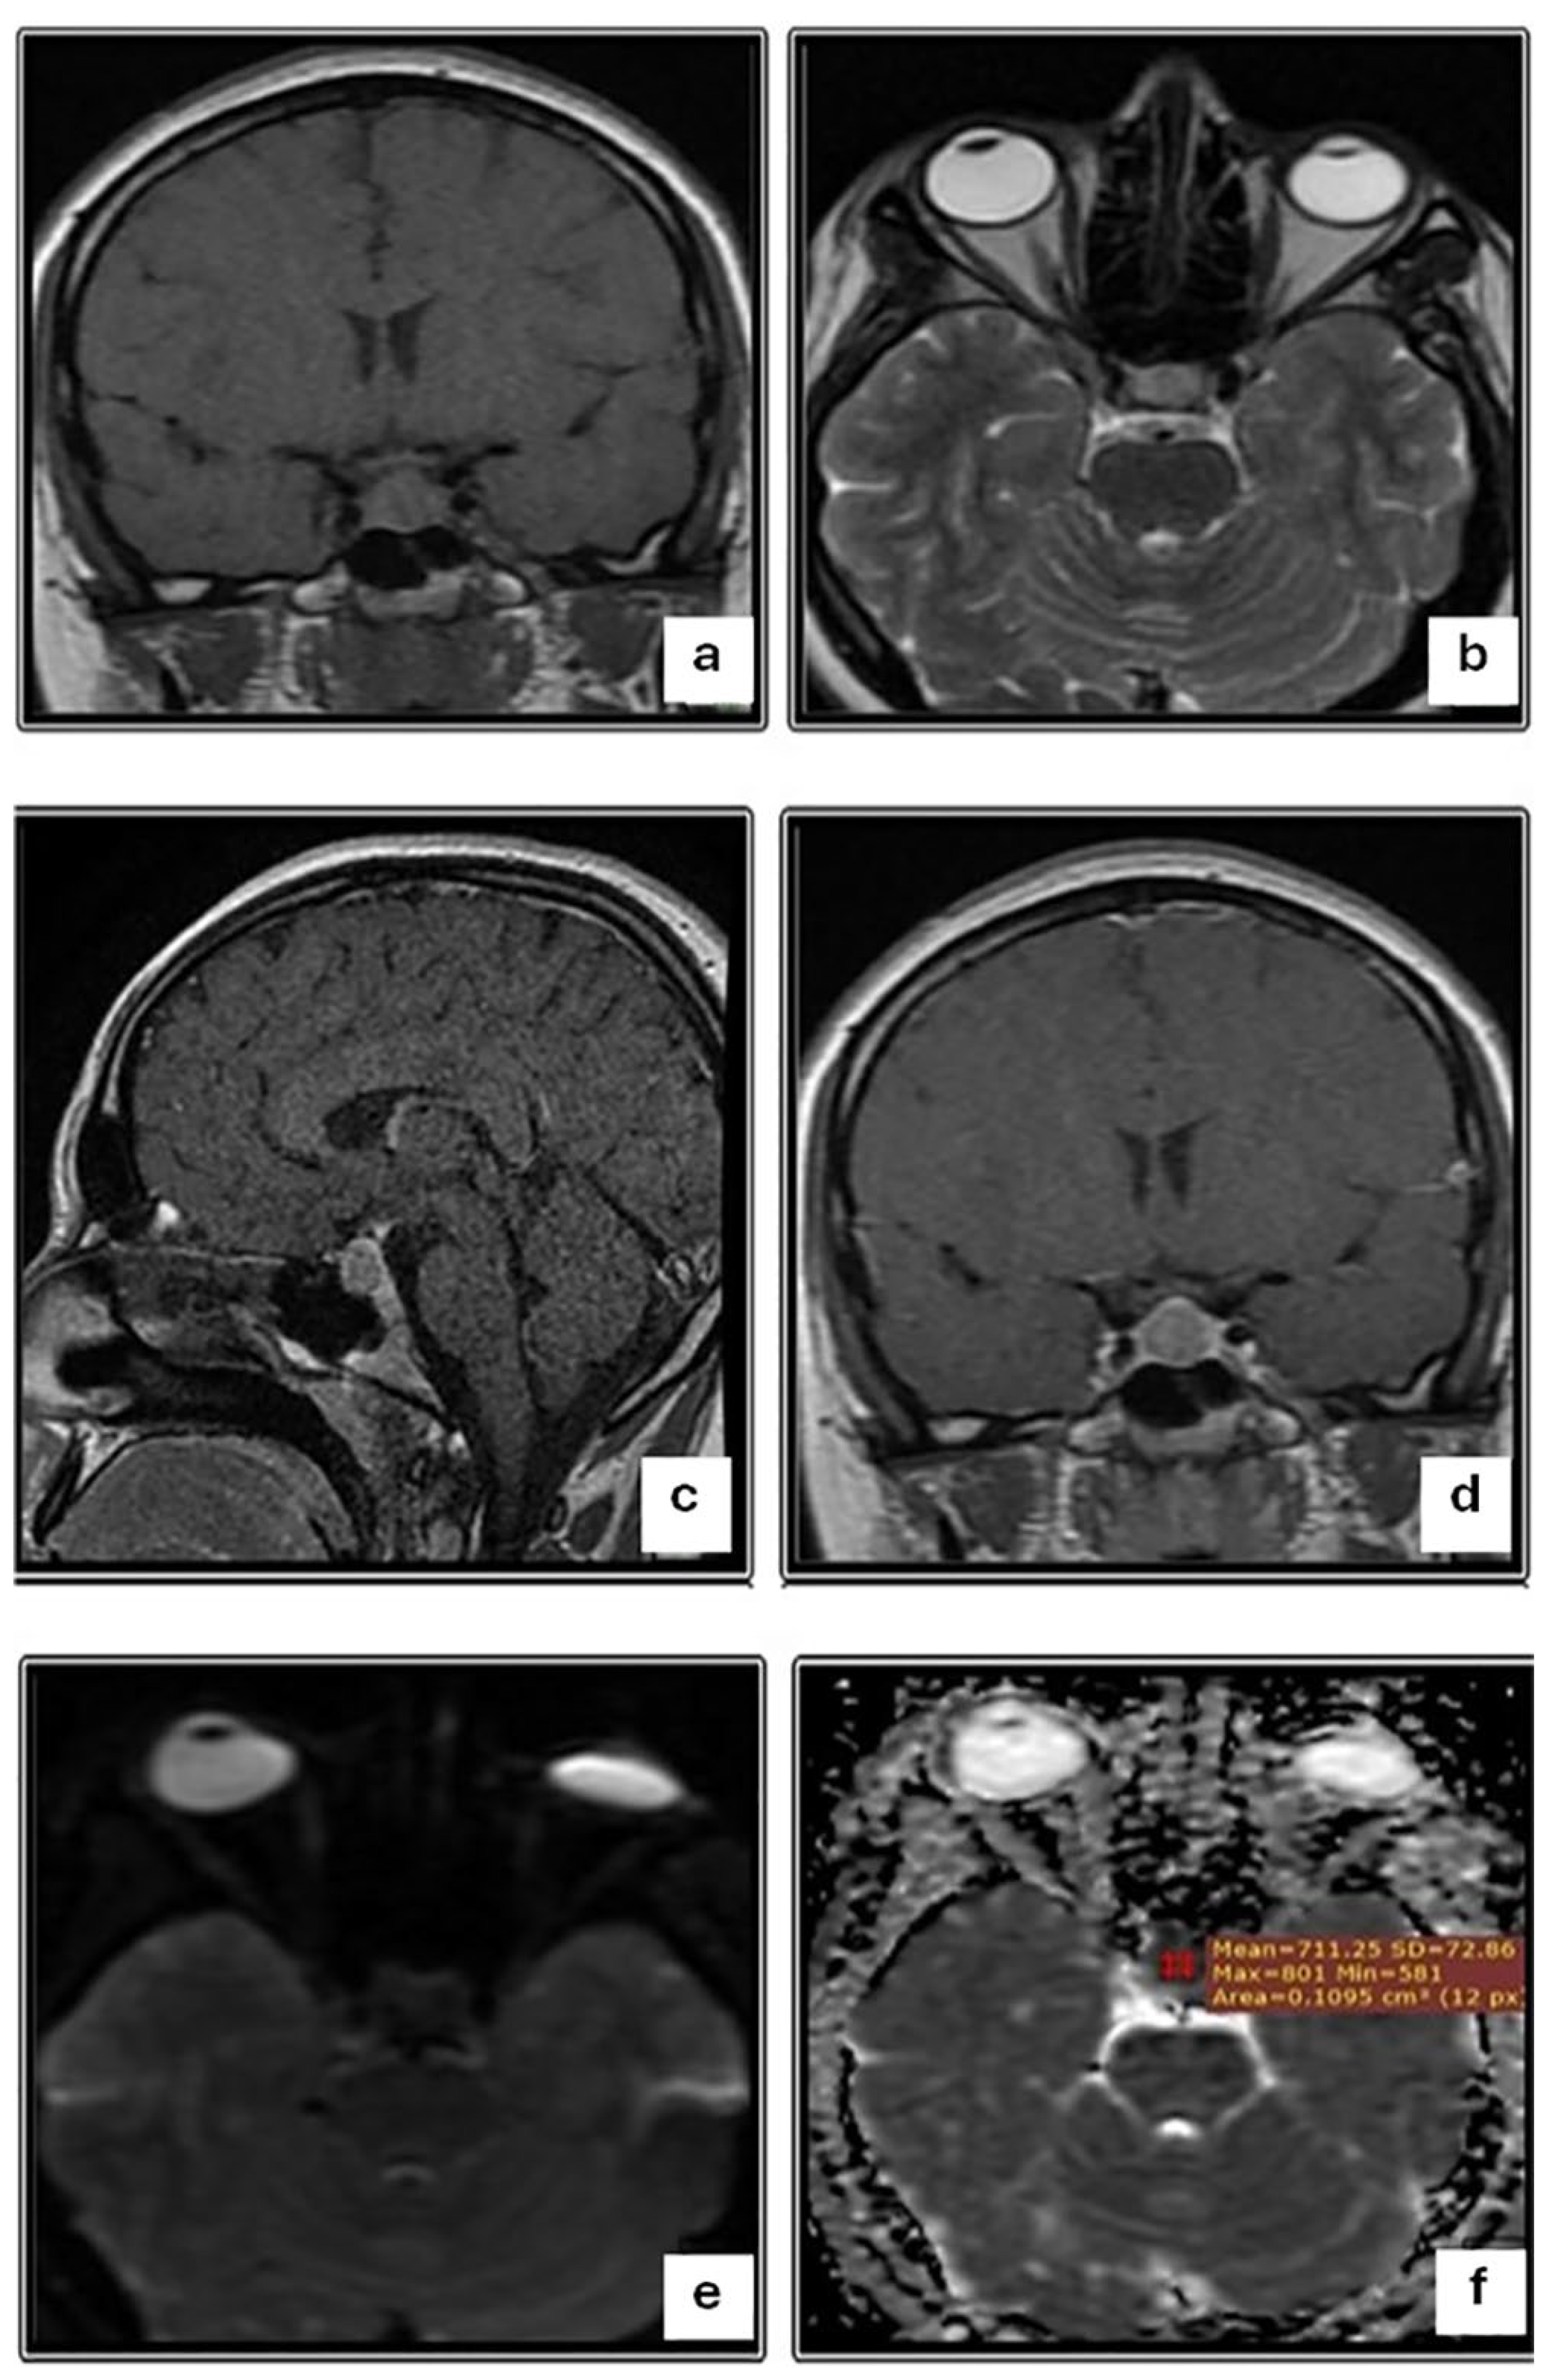

| Macroadenoma | p-Value | |||

|---|---|---|---|---|

| Total (n = 45) | Aspirable (n = 27) | Non-Aspirable (n = 18) | ||

| DWI (b 100) | <0.001 | |||

| Iso-intense | 9 (20.0) | 9 (33.3) | 0 (0) | |

| Hypo-intense | 15 (33.3) | 0 (0) | 15 (83.3) | |

| Hyper-intense | 21 (46.7) | 18 (66.7) | 3 (16.7) | |

| ADC map | 0.004 | |||

| Hypo-intense | 21 (46.7) | 18 (66.7) | 3 (16.7) | |

| Hyper-intense | 15 (33.3) | 0 (0) | 15 (83.3) | |

| ADC value, Mean ±SD (range) | 0.72 ± 0.25 (0.40–1.10) | 0.54 ± 0.19 (0.42–0.90) | 0.95 ± 0.08 (0.90–1.10) | 0.008 |